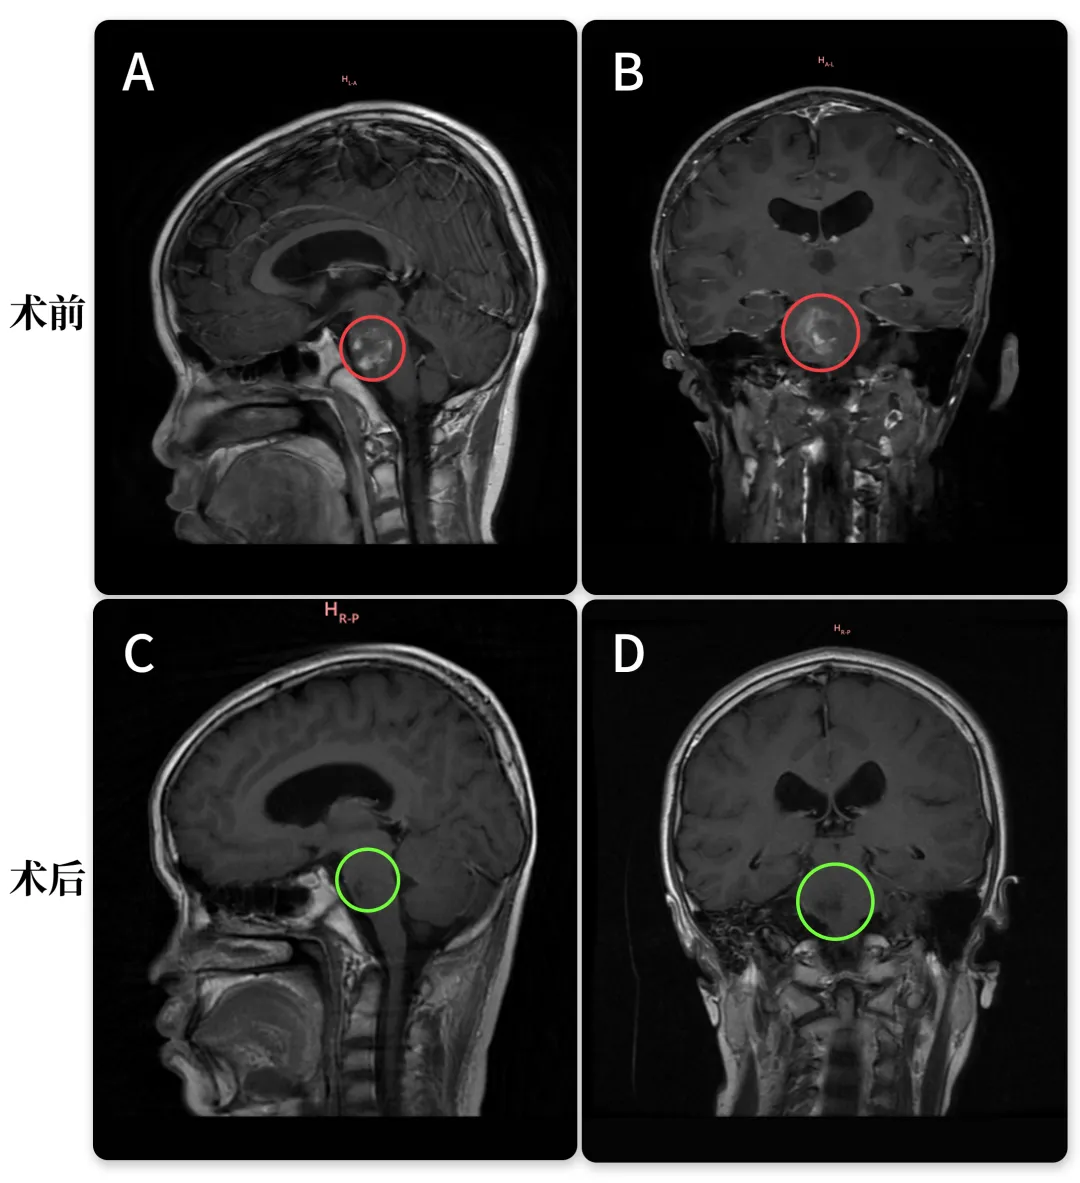

30岁的文文罹患丘脑基底节海绵状血管瘤,经历多次出血。治疗选择从保守到药物,无法有效缓解症状。症状甚至不断加重,右眼视力下降明显,右下肢无力,步态不稳,复查MRI提示病变增大。但是医生考虑手术并发症和风险过大,还是建议保守治疗。然而多次出血已经无法保守治疗。通过INC远程咨询巴教授之后,巴教授表示:畸形位于大脑的一个关键区域,但对我来说是可以做手术的。由于反复的出血和病人年龄较年轻,是有手术指征,手术也是可行的。北京时间2023年3月23日,文文成功手术。手术难度堪比脑干,早在30年前巴教授已有成功案例发表!

术前术后影像对比